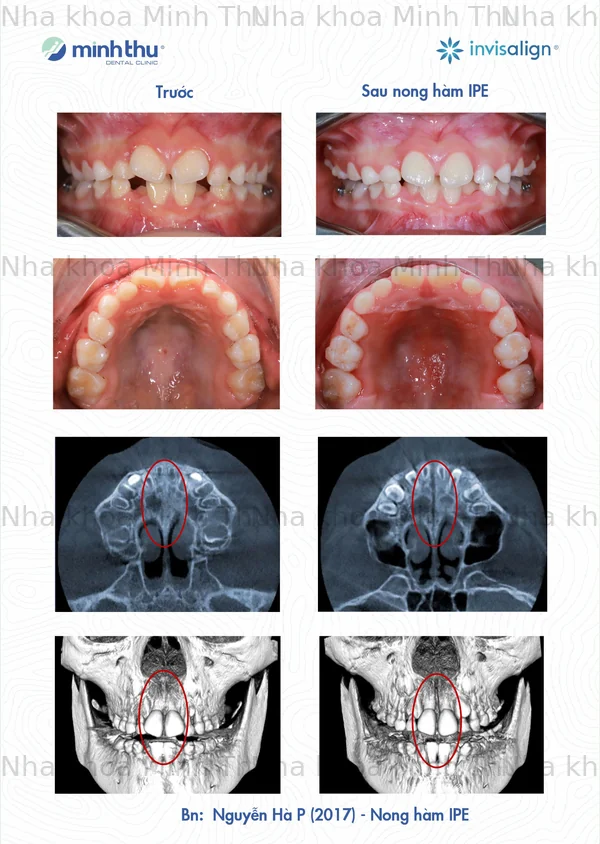

Một số ca nong hàm IPE tại Nha Khoa Minh Thu, kết quả phụ thuộc vào tình trạng và mức độ đáp ứng điều trị của mỗi bệnh nhân.